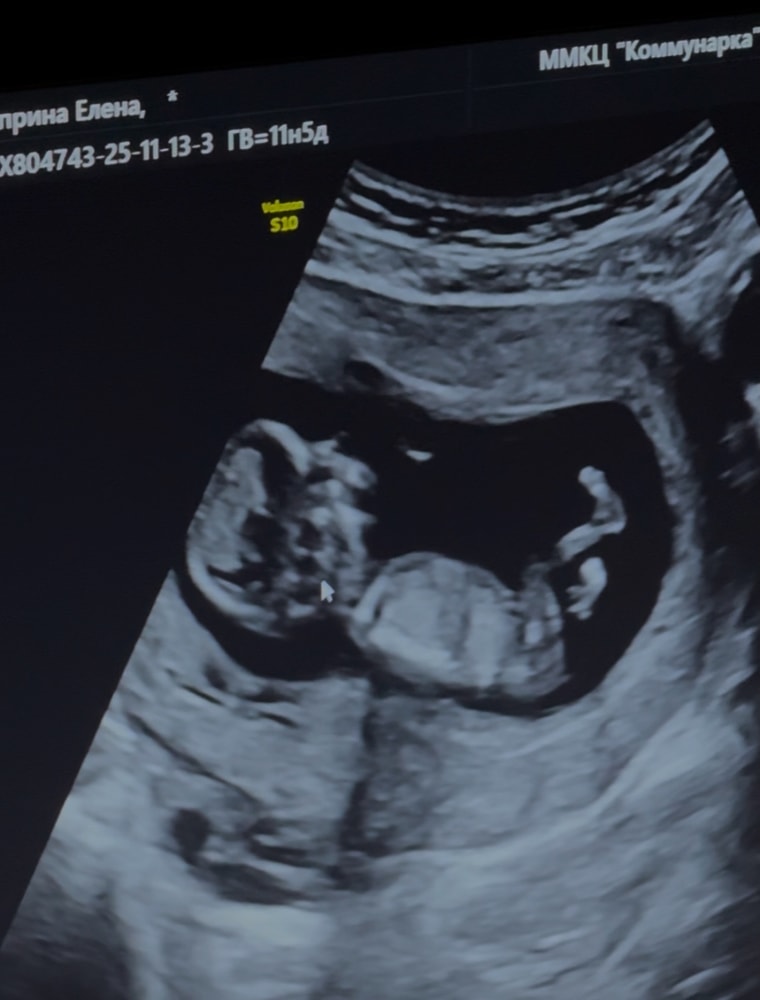

Все хорошо: анатомия, органы🙏🏻 Скользил кроха так смешно, отталкиваясь ножками🥹

Развитие чуть опережает (где-то 12н6д, в чем-то 13н2дн, в итоге по УЗИ ставят в совокупности - 12н2д (по переносу 12 ровно, по мес. 11н5д).

КТР - 59 мм

ТВП - 1.6 мм

ЧСС - 163 уд/мин🫶🏼

В пуповине 3 сосуда. Плацента идеально расположена - по задней стенке. Для кесаренных это просто шикарно! Но низко. Надеюсь, с ростом малыша, поднимется🙏🏻Шов (рубец) в норме. Шейка матки - 39 мм.